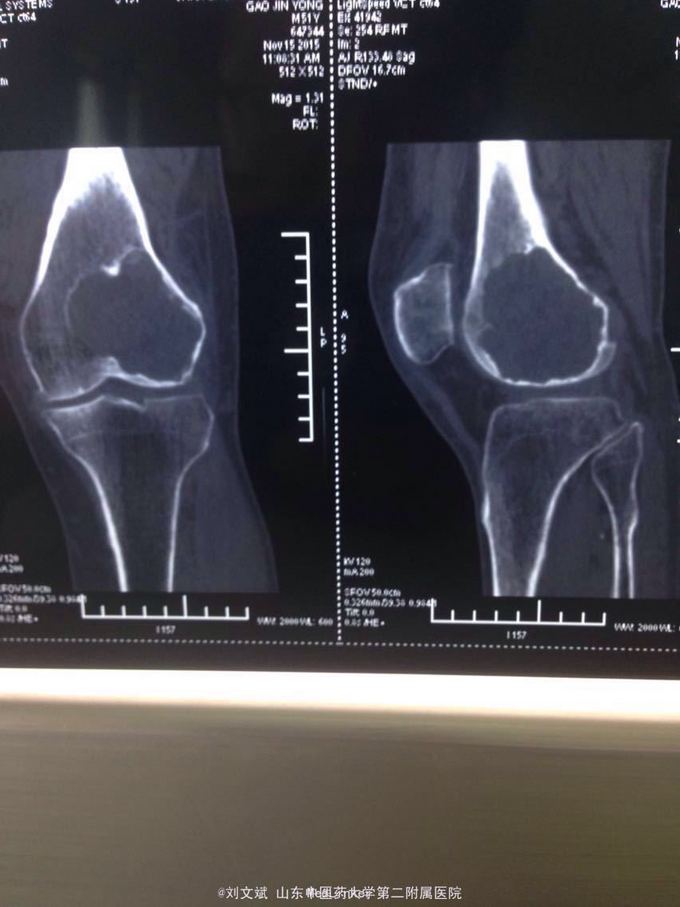

男性51岁,左膝关节疼痛不适10余年。因症状较轻,不影响活动,未曾系统诊治。一月前因扭伤致疼痛加重,拍片检查,见股骨远端骨质异常,进一步行CT示股骨髁占位病变,考虑骨囊肿。既往有高血压,糖尿病病史。近期无低热,体重下降。

左膝关节外观皮色正常,无明显肿胀,屈伸活动未见明显受限,外髁轻度压痛,侧方应力及抽屉试验阴性,半月板回旋挤压试验阴性,浮髌试验阴性。肢端感觉,血运正常。

诊断:左股骨远端占位 因皮质完整,行手术开窗刮除,自体髂骨及同种异体骨混合植骨填充治疗。切取组织送病理检查

刮除占位组织如图所示,送病理检查了,结果还没回来。 没有全身症状,像是原发灶,骨皮质完整,没有明显骨膜反应请专家们看看,什么可能性比较大? 补上病理结果和术后片子